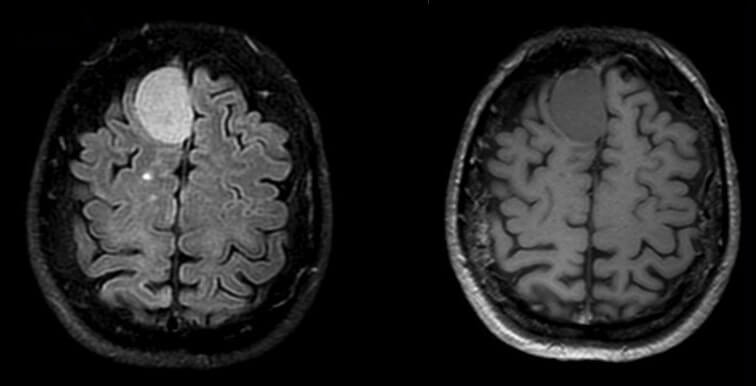

IRM cérébrale (coupes axiales FLAIR et T1) : méningiome frontal para-sagittal droit homogène